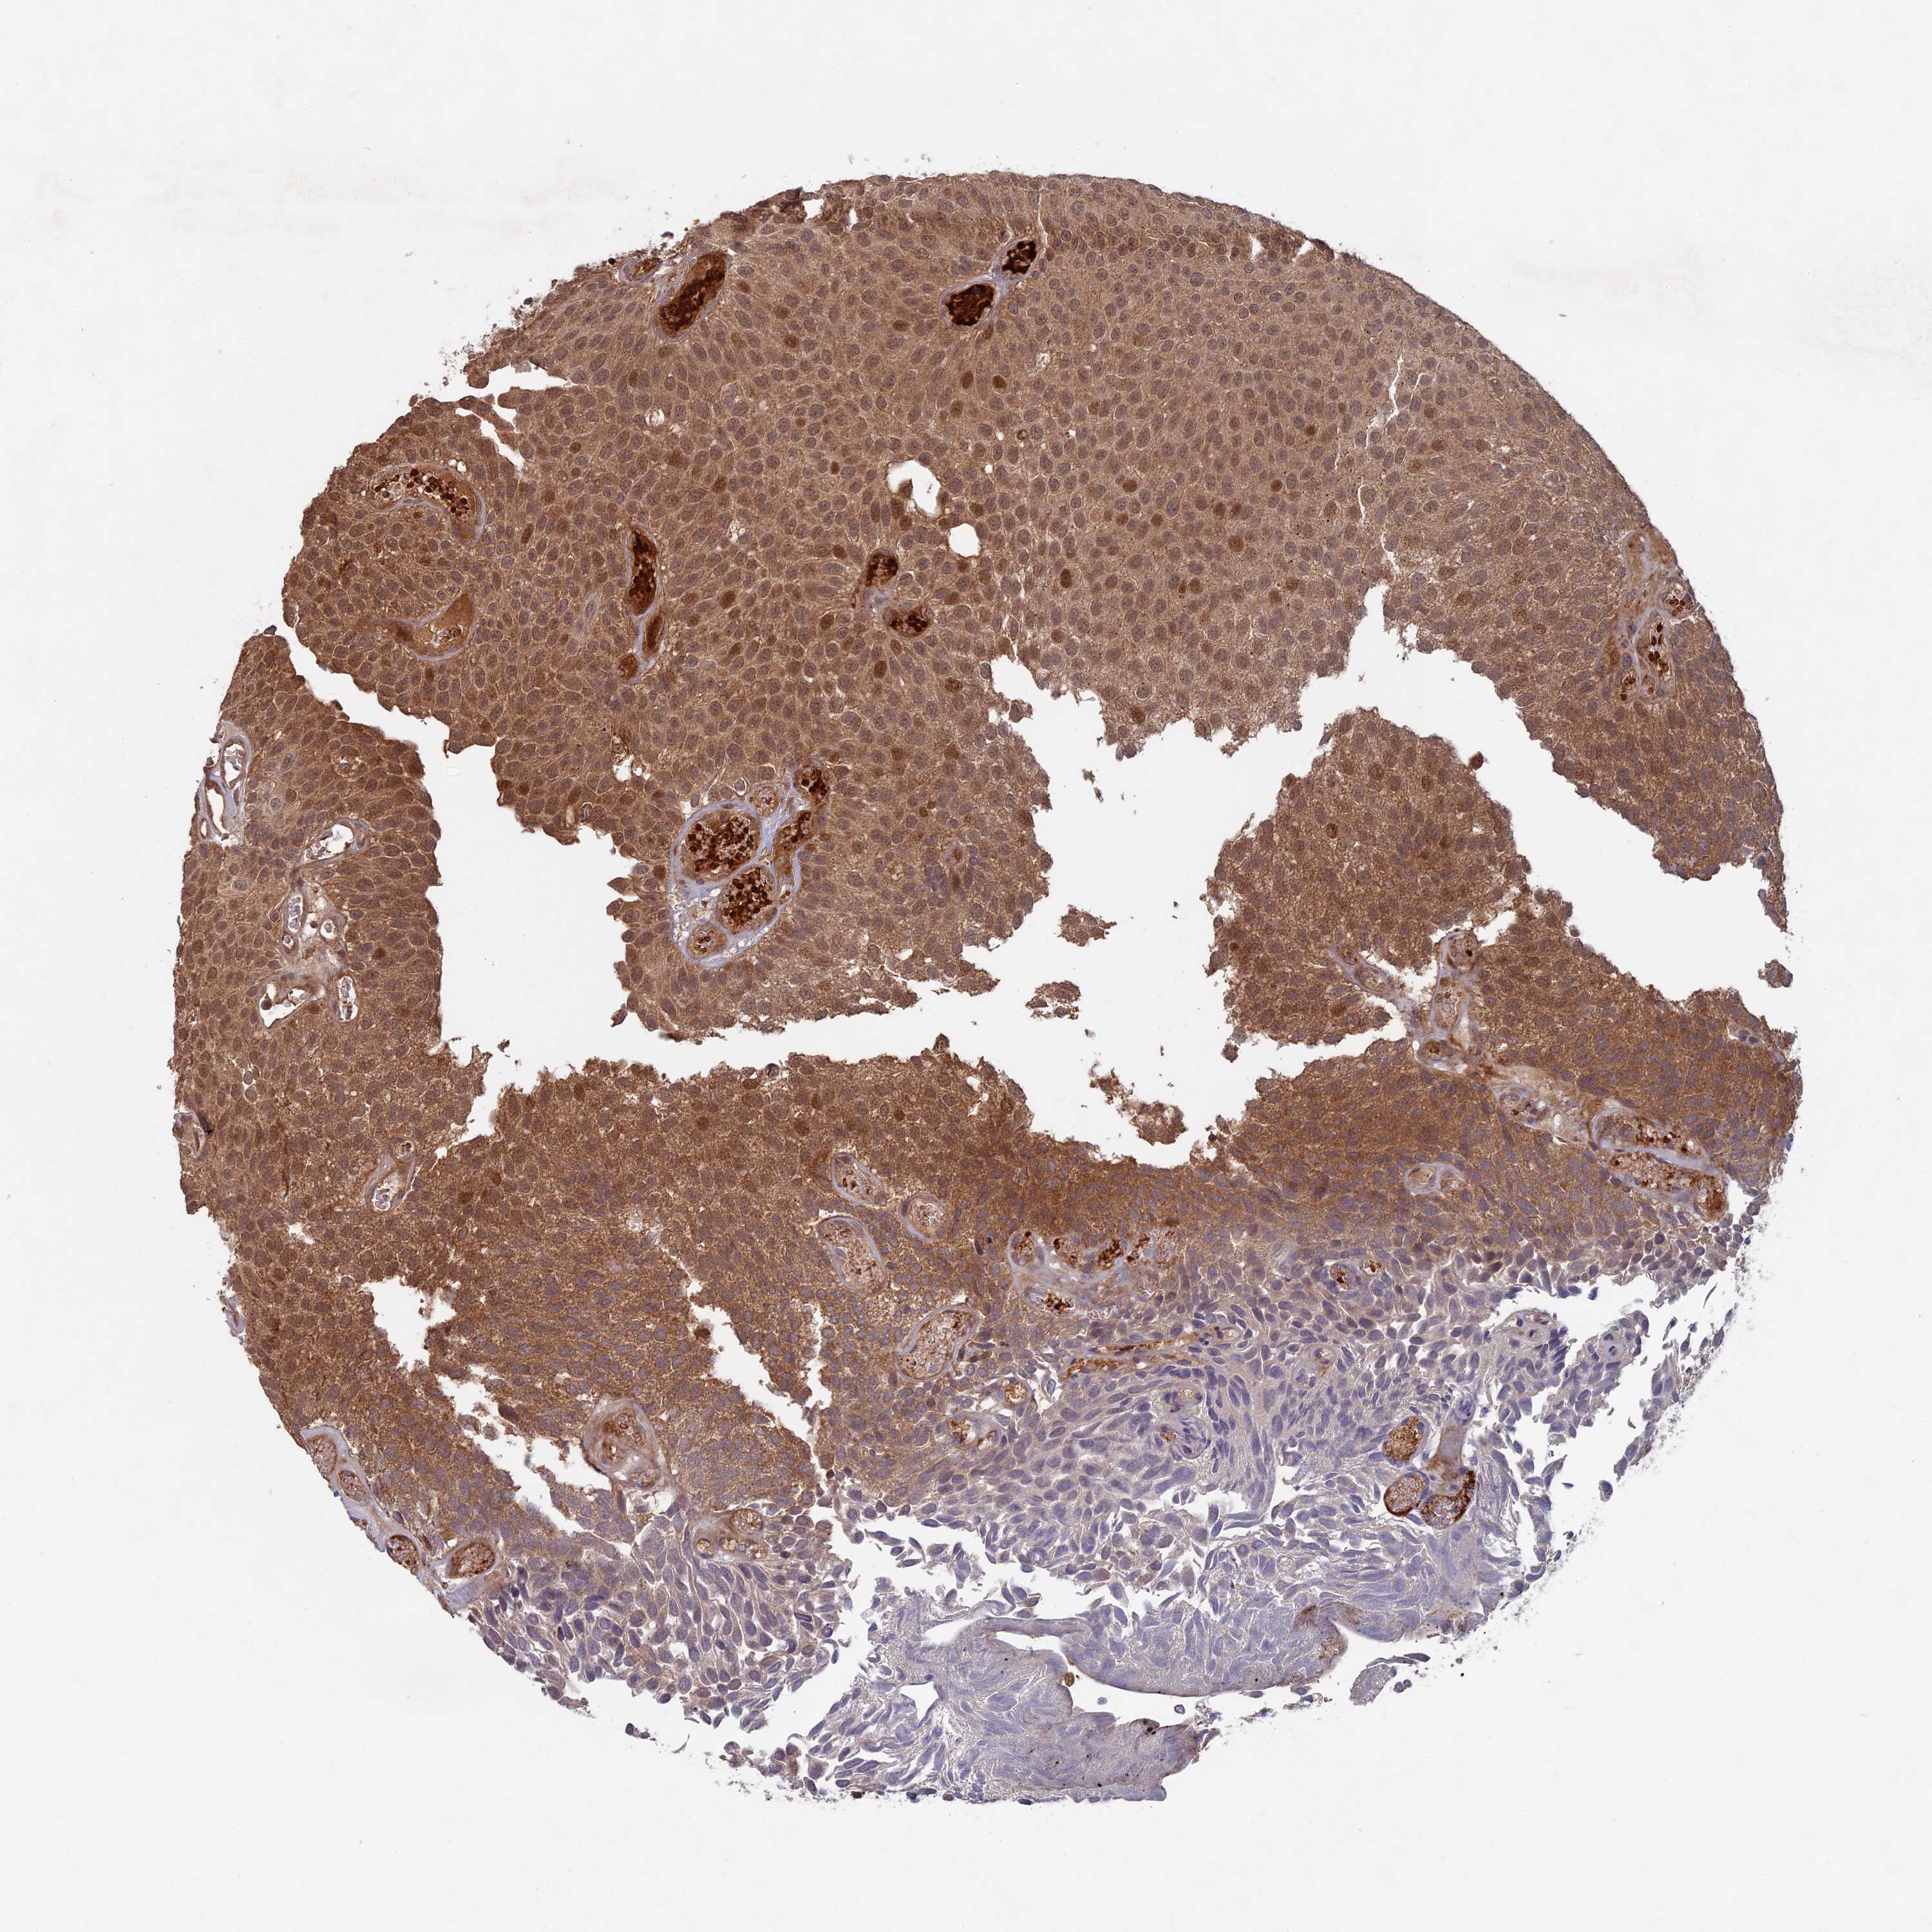

UROTHELIAL CANCER - Protein expressioni

A mouse-over function shows sample information and annotation data. Click on an image to view it in a full screen mode. Samples can be filtered based on level of antibody staining by selecting one or several of the following categories: high, medium, low and not detected. The assay and annotation is described here.

Note that samples used for immunohistochemistry by the Human Protein Atlas do not correspond to samples in the TCGA dataset.

Antibody stainingi

Antibody staining in the annotated cell types in the current human tissue is reported as not detected, low, medium, or high, based on conventional immunohistochemistry profiling in selected tissues. This score is based on the combination of the staining intensity and fraction of stained cells.

Each image is clickable and will lead to virtual microscopy that enables deeper exploration of all samples and also displays staining intensity scores, fraction scores and subcellular localization as well as patient and tissue information for each sample.

Antibody HPA039683

Antibody HPA040776

Urothelial carcinoma, High grade

Urothelial carcinoma, Low grade